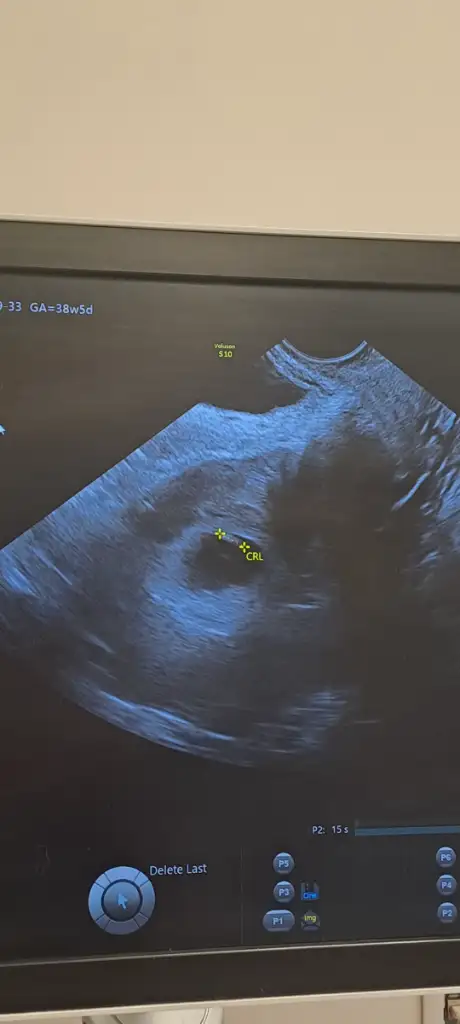

Kızlar ultrason resimlerinizi ve cinsiyetinizi paylaşında nub teorisi tutuyor mu bakalım

Kızlar bebişlerinizin ultrason resimlerini ve cinsiyetini kaçıncı haftada olduklarını yazında kendi ultrason resimlerimizle kıyaslayıp fikirde bulunalım. Nub teorisi, kafa şekli, kemik yapısından cinsiyet teorileri tutuyor mu bakalım bir🥰